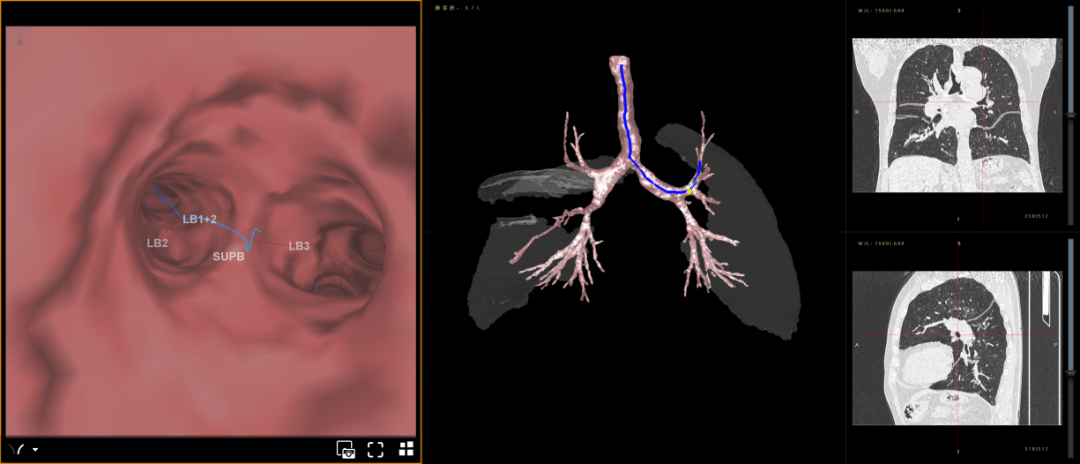

呼吸一病区医疗团队评估后认为邹嗲符合热蒸汽消融肺减容术手术指征,在取得患者及家属同意后,特请胸外科、麻醉科、心内一科、影像科、肺功能室等科室开展多科会诊。会诊同意手术后,7月24日,手术团队在静息复合全麻下为邹嗲行经支气管镜热蒸汽消融肺减容术,手术进展顺利,目前邹嗲已转入普通病房,呼吸情况得到明显改善,正在日益康复中。

利用支气管镜介入技术,通过消除过度膨胀功能低下的病变肺段,为周边更优功能肺段创造空间方式,来提高患者肺功能和生活质量。手术时间15分钟左右即可完成,无植入物,安全性高,减容效果3-6个月逐渐显现,6个月达到最佳,是中重度慢阻肺病人一项新的治疗方案。

是指通过经支气管内窥镜热蒸汽消融治疗术将热的水蒸汽输送到靶肺段进行消融以实现肺减容,减容后为正常的肺组织留出空间,提升病人呼吸的机械效率。适用于GOLD评级3-4级,经充分药物及康复治疗不佳的非均质性(双上肺)肺气肿患者的治疗。